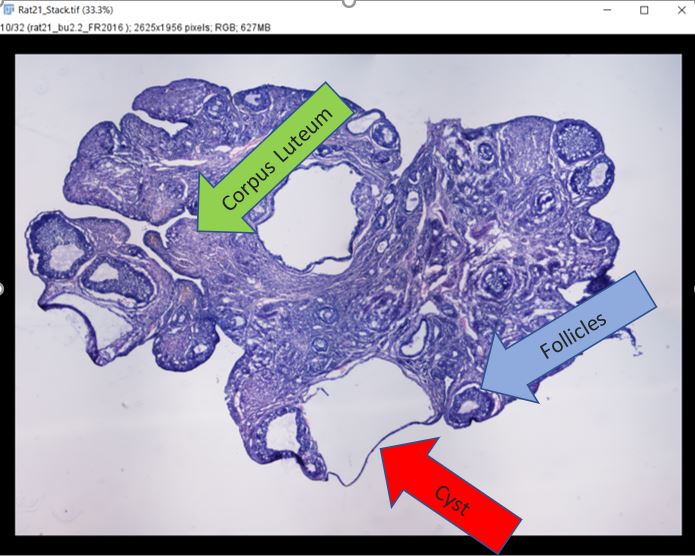

Because of COVID-19, my summer plan was canceled. However, I connected with a Dr. Toporikova from the Biology department at W&L. This research opportunity was perfect since it could be safely done at home. My project this summer was to build a computational algorithm to classify different structures of the rat’s ovaries. The goal is to design a computer learning code that will help researcher distinguish between follicles, cysts, and corpus luteum without any bias. My background was in neuroscience with little coding experience. However, this set back did not stop me from doing what I love, research. For 14 weeks, I learned how to code in Python to an intermediate proficiency, using my new skills to process images and data collections.

The project is divided into two parts: 1) collecting images of follicles, cysts, and corpus luteum and 2) write a computer learning algorithm to recognize the three different structures. For the first part, I must learn to distinguish the three structures myself which came with practice. The process was slow but I eventually gain a new skill to analyze tissues samples and pull out relevant features. Toward the end of summer, I was chosen by my PI to mentor a new student. I taught her to identify the different ovaries’s structures. This is a very rewarding experience for me because it teaches me to be a better communicator and mentor while showing me how much I have progress in 10 weeks. The second part of research was to build a code that would do all the work that people could do. Using my new skill in Python, I work with my team to resize images, put filters on them, sort them into csv files, and ultimately run a code on the collected images to classify the structures. We have gotten 99% accuracy when identifying cyst versus corpus luteum. In the future, we hope to imporve the accuracy for identifying cysts and follicles since there were lots of similarity between them. We also hope to write a code that will distinguish between all three structures.